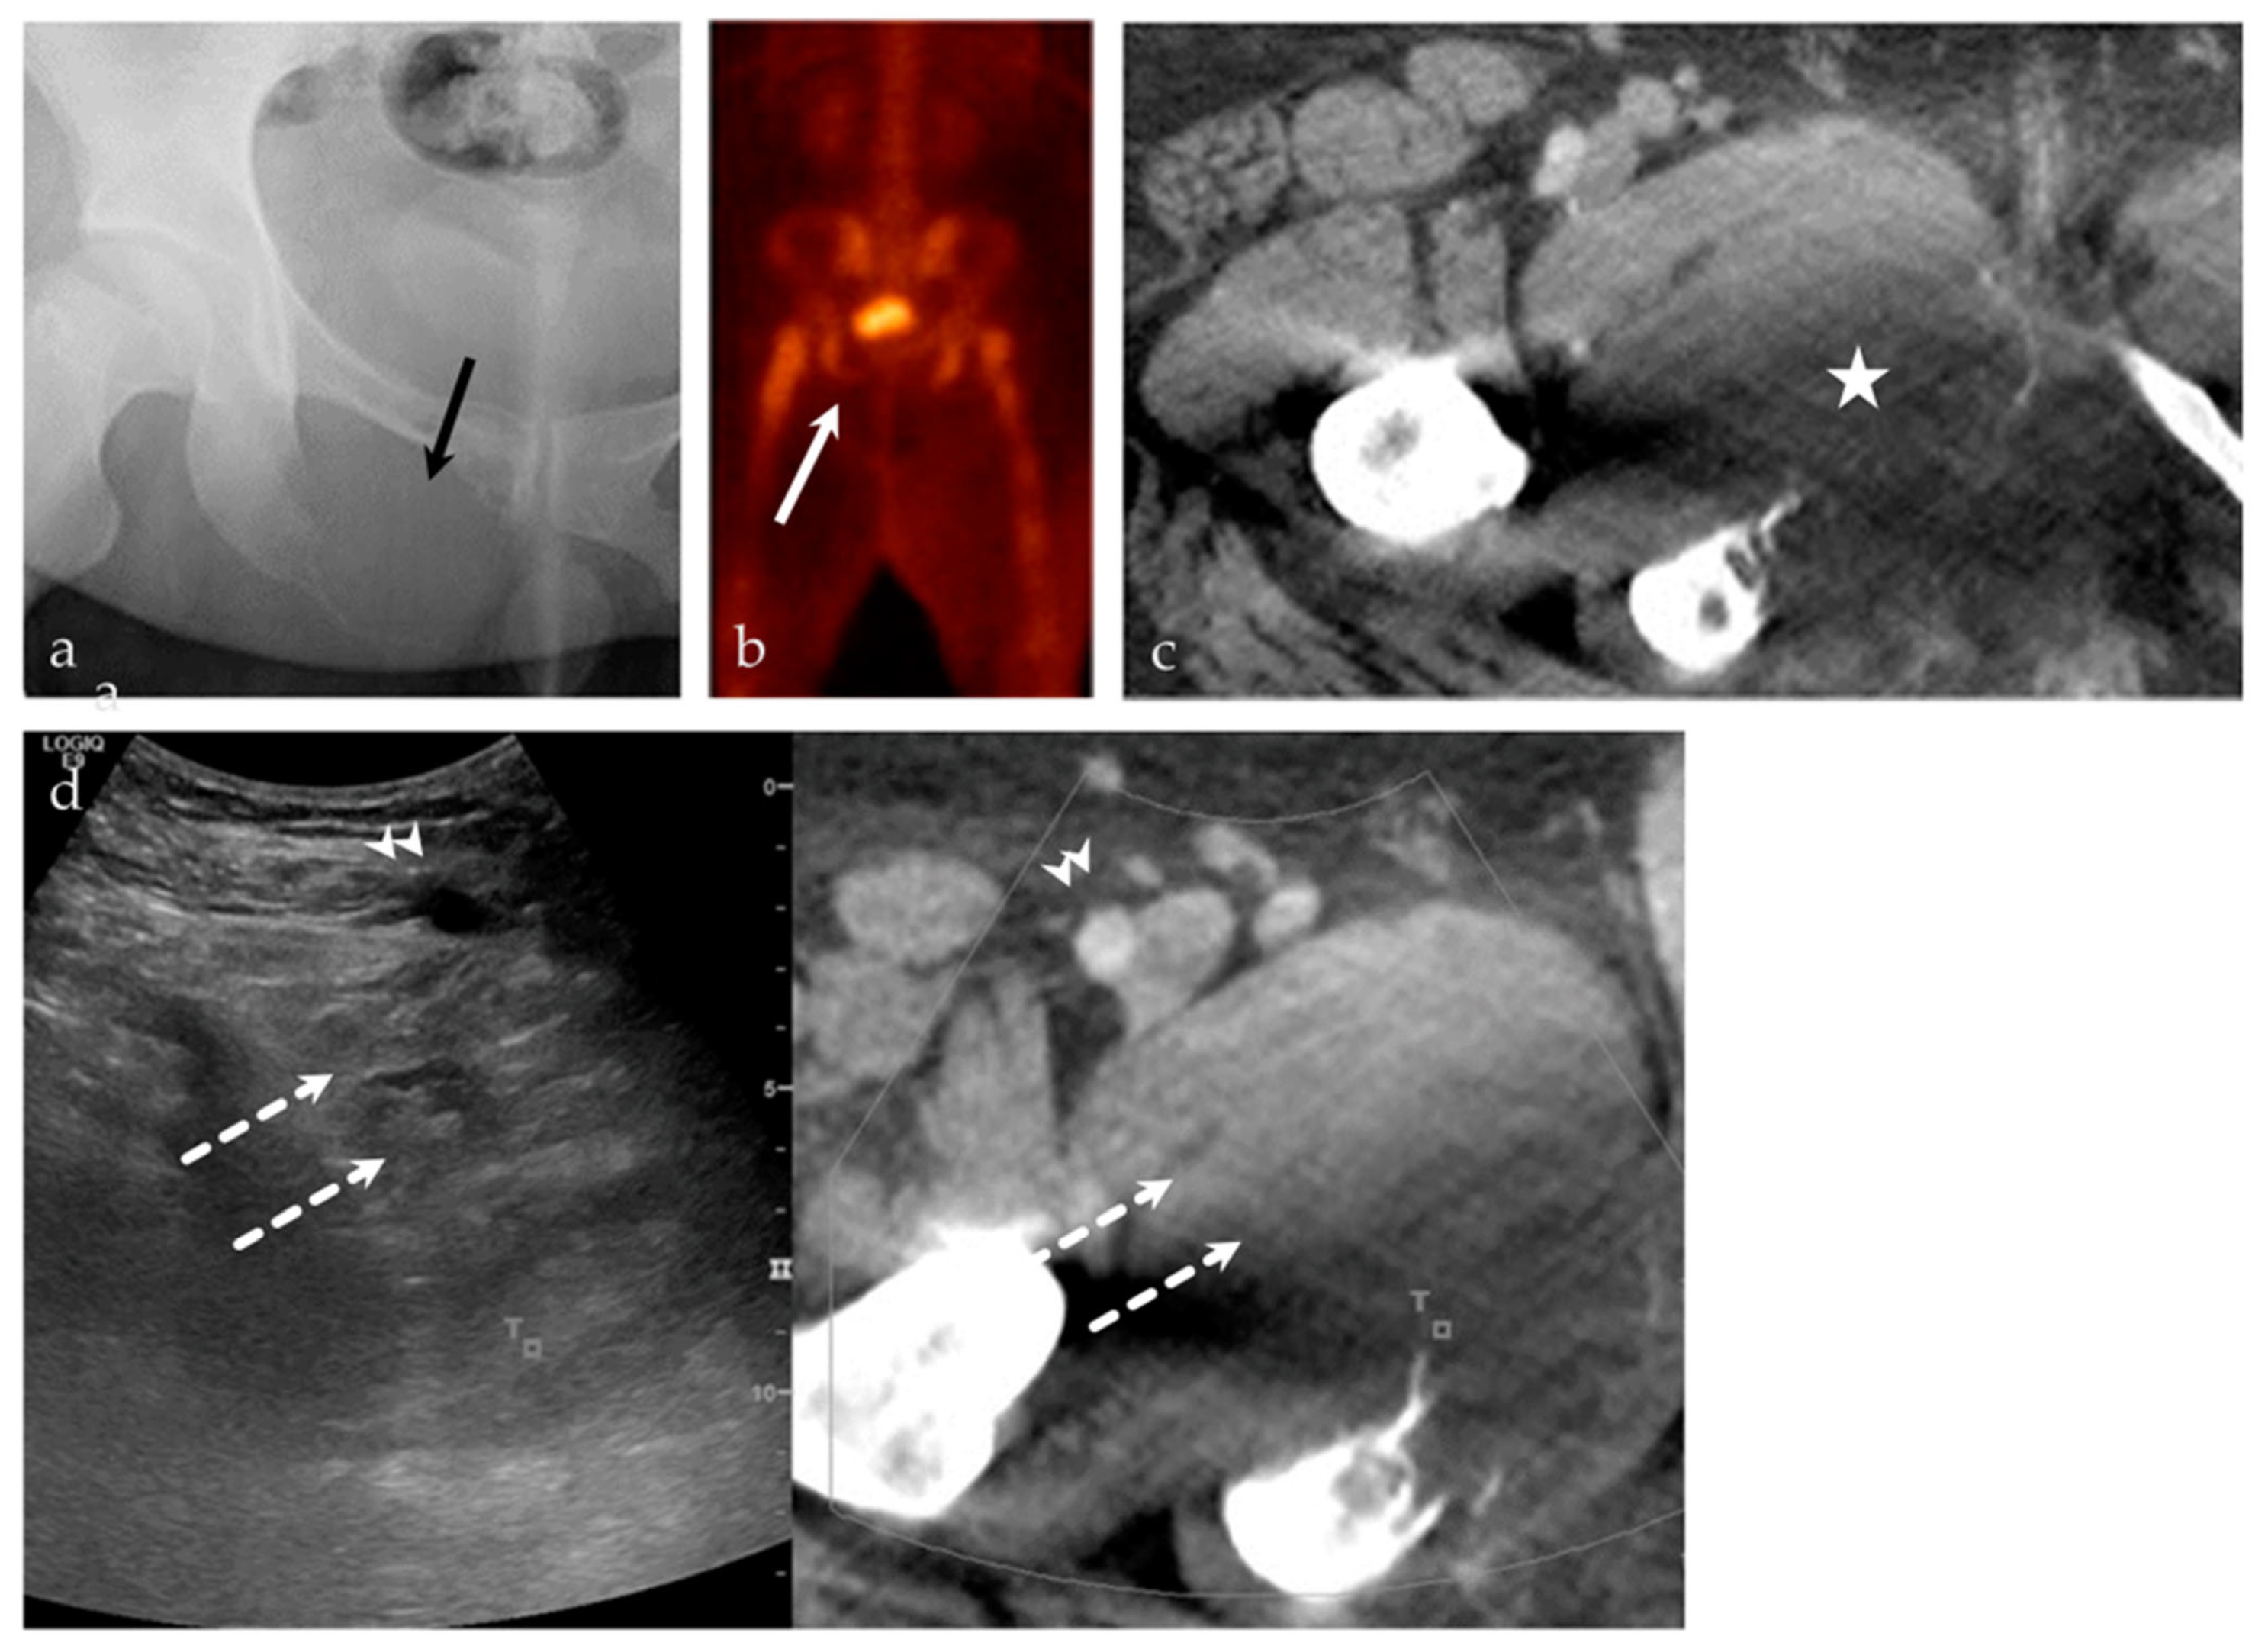

| 63/F | Left posterior iliac bone | US-PET | Metastatic disease, breast carcinoma | Neoplastic, malignant |

| 24/M | Right inferior pubic ramus | US-CT | Ewing sarcoma | Neoplastic, malignant |

| 51/M | Left parasymphyseal pubis | US-CT | Fibrous dysplasia | Metabolic |

| 54/F | Right acetabulum | US-CT | Metastatic disease, endometrial carcinoma | Neoplastic, malignant |